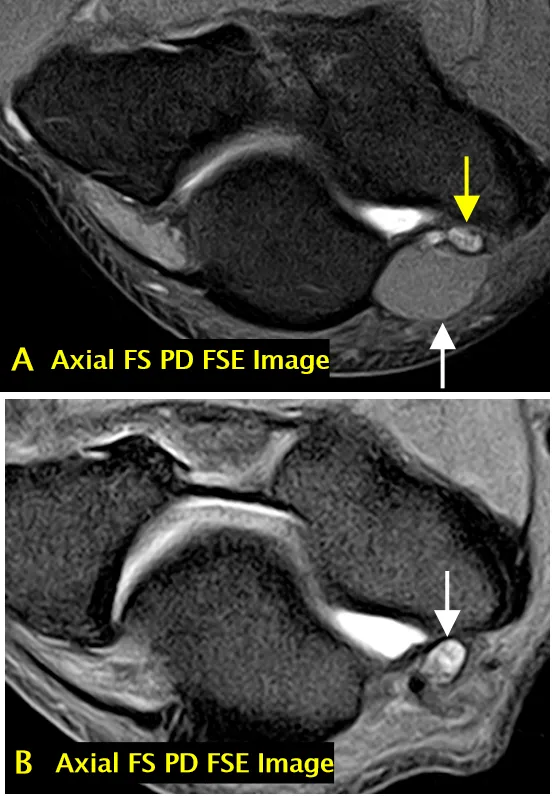

• 肘肌上髁肌(A 图):人群发生率约 25%(白色箭头标注),可能与尺神经卡压相关(黄色箭头标注);成像序列:轴面脂肪抑制 PD 加权图像;

• 液体敏感序列上信号增高的尺神经(B 图):约 60% 无症状人群可见(箭头标注);成像序列:轴面脂肪抑制 PD 加权图像;

• 完整的内侧副韧带前束(AMCL)复合体(C 图):其远端附着点可位于关节线下 3mm 处(箭头标注);成像序列:冠状面 PD 加权图像。